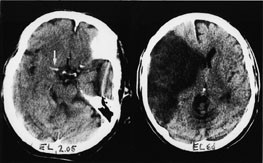

De følgende eksempler er hentet fra pasienter innlagt i Nevrologisk avdeling, Haukeland Sykehus, med akutt cerebral iskemi og undersøkt med CT innen tre timer og ti minutter etter symptomdebut (bildet til venstre, fig 1 – 4) og med oppfølgende CT (bildet til høyre, fig 1 – 4). Bildene illustrerer de forannevnte kardinaltegn (tab 1).

Omfattende mediaskade i mer enn en tredel av a. cerebri medias forsyningsområde (fig 4). Hypodenst vev ved CT betyr irreversibel skade. Hypodensitet oppstår som følge av cytotoksisk ødem. Ødemet fører gradvis til utplanert relieff på hjerneoverflaten og i insularegionen. Et indirekte tegn kan være redusert volum av fissura Sylvii og/eller mindre ventrikkelstørrelse på den aktuelle siden.